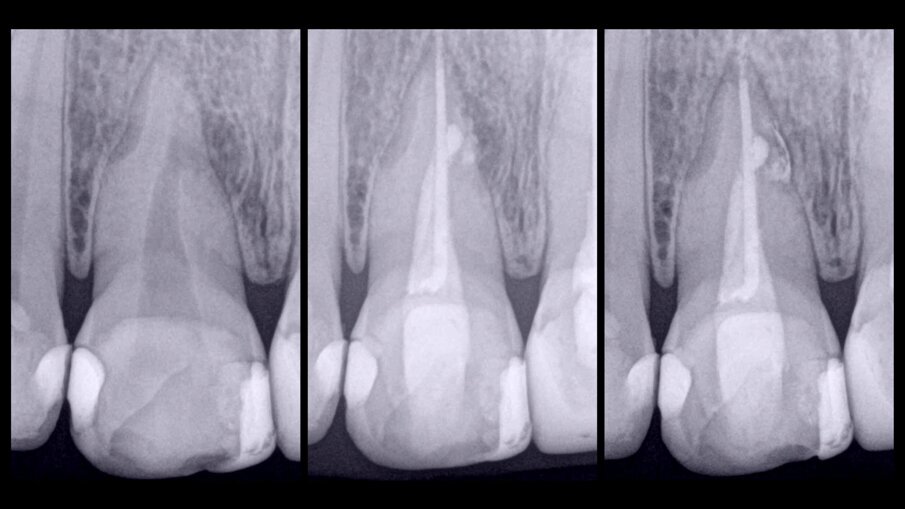

Figs. 6a–c: Radiographic sequence of the treatment performed in tooth #11. Initial radiograph. The root resorption and lateral radiolucent area were evident (a). Working length measurement at the level of the resorption (b). Root resorption repair with a calcium silicate-based material (c).

Figs. 7a–c: Radiographic sequence of the treatment performed in tooth #11. Initial radiograph. The root resorption and lateral radiolucent area were evident (a). Master cone fitting at the level of the complete working length (b). Completed root canal therapy (c).

Fig. 8: Radiographic sequence of the treatment performed in tooth #11. Initial radiograph. The root resorption and lateral radiolucent area were evident (a). Completed root canal therapy (b). Three-year follow-up radiograph showing complete healing of the lateral radicular radiolucent area and the correct sealing of the resorption (c).

During the first appointment for root canal therapy, it was not possible to reach the complete length of the root canal, because the files tended to go inside of the mesial resorption. It was decided to seal the resorptive defect (Fig. 6a–c) using CeraSeal sonically activated using the EQ-S device (Meta Biomed; see video below).

At the second appointment, the material placed at the resorption was completely hard. That hard barrier allowed the file to pass through the entire length of the physiological root canal. The root canal therapy was finished using CeraSeal as the endodontic sealer (Fig. 7a–c). The three-year follow-up radiograph showed complete healing of the lateral radicular radiolucent area (Fig. 8a–c).